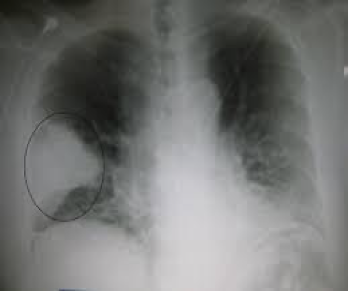

Diagnostic Evaluation

CXR –usually needed to establish diagnosis –prognostic indicator –rule out other disorders –may help in etiological diagnosis

CT scan of Chest –Radiologic findings may not be present in the early stages of the disease, especially in the presence of dehydration, or may be difficult to be interpreted in the obese or those with a history of lung disease. A CT scan can give additional information in indeterminate cases